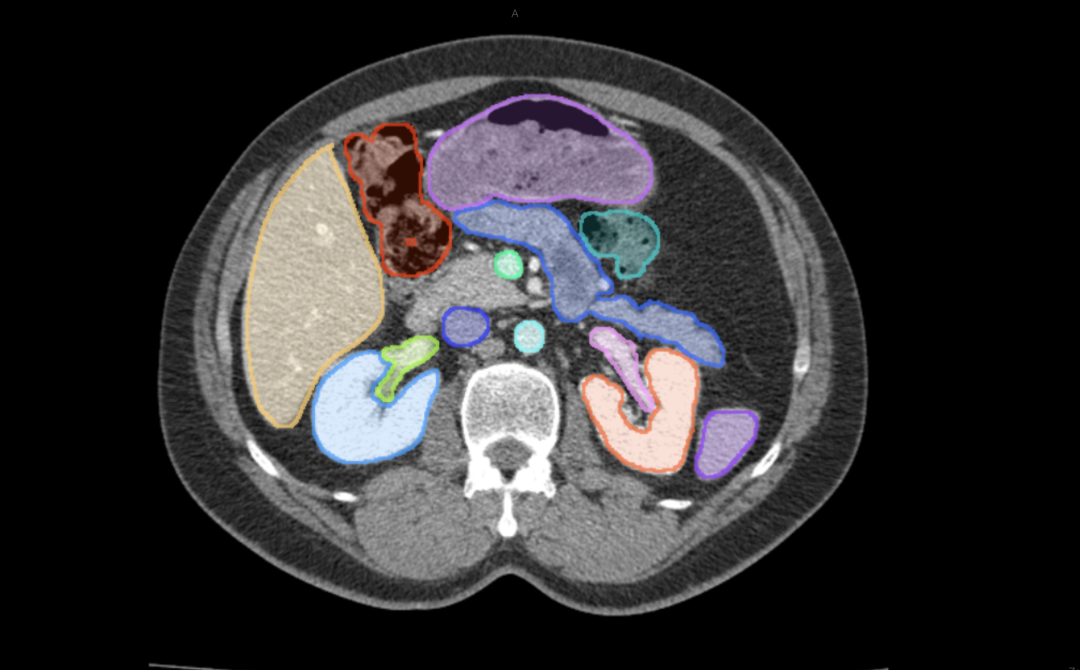

腹腔器官标注

医学影像具有特殊性和复杂性,不同于日常的二维图像,医学影像都是三维数据,目标对象的边缘时常不够清晰,分割难度大,专业性强。基于这些特点,东软智能医疗科技研究院通过深入研究在医学影像领域预训练大模型技术,通过“预训练大模型+下游任务微调”的方式,有效地从大量标记和未标记的数据中捕获知识,扩展模型的泛化能力,解决了模型碎片化问题,为人工智能+医疗提供了崭新的技术路线,为突破现有算法性能的瓶颈提供了无限可能。同时,结合了东软自身积累的多种多样的带有标注数据的大量数据集,对预训练大模型进行二次训练,并针对医学影像的三维特点进行优化,推出了医学影像分割大模型MISM,进一步提高了医学影像标注的质量和效率。

飞标平台借助医学影像分割大模型MISM进行了全新升级,4.0版实现了通过一个点、一个边界框,一键分割出病灶或解剖结构的功能,能够更精准的连续逐层标注。此外,飞标4.0版支持集成第三方的预标注算法,使飞标平台具有了功能可扩展的开放性。